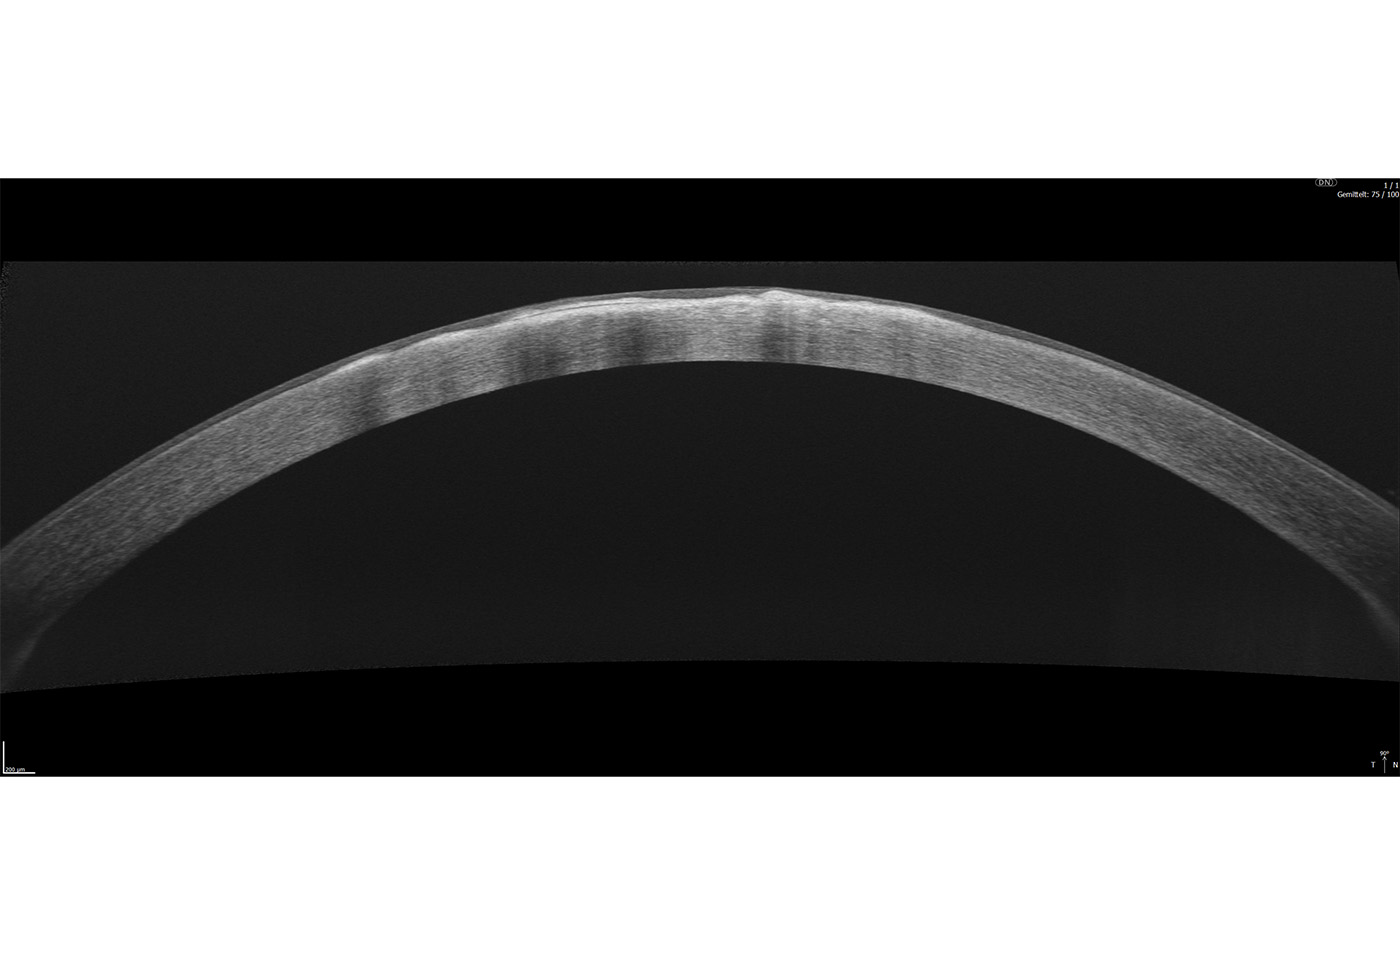

Full Range-Aufnahmen

Das Extended Depth Retina Imaging, welches auf der Full Range-Technologie basiert, bietet Scans mit größerer Tiefe für eine zuverlässige und bequeme Kontrolle von schwierigen Fällen. Dank der Scans mit großer Tiefe ist dieser neue Bildgebungsmodus perfekt für die Diagnose von sehr stark kurzsichtigen Patienten geeignet. Außerdem bietet sie einen Überblick über die gesamte Vorderkammer, von Hornhaut bis zur Augenlinse.

Anterior:

- Pachymetrie

- LASIK Flap Vermessung

- Kammerwinkelmessung

- Weitwinkel-Scans